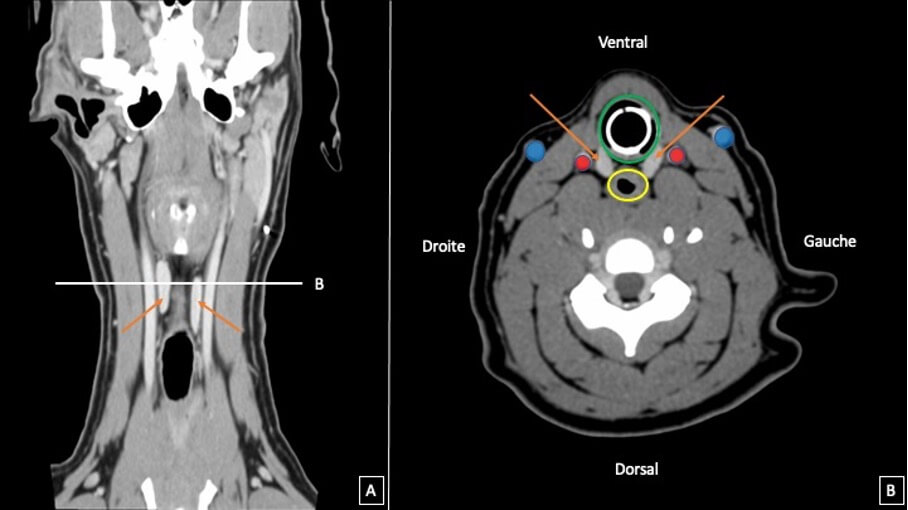

Les repères vasculaires jouent un rôle clé dans l’identification des structures cervicales. Les veines jugulaires externes et les artères carotides communes sont paires, visibles sous forme de structures tubulaires en coupe longitudinale et circulaire en coupe transverse, présentant une lumière anéchogène et une paroi hyperéchogène, plus épaisse pour les structures artérielles que veineuses. Ces vaisseaux servent de repères pour localiser les glandes thyroïdes et parathyroïdes.

Coupe tomographiques cervicales chez le chien mettant en évidence les rapport anatomiques entre la trachée (vert), l’œsophage (jaune), les artères carotides communes (rouge) les veines jugulaires externes (bleu) et les lobes thyroïdiens (flèches oranges).